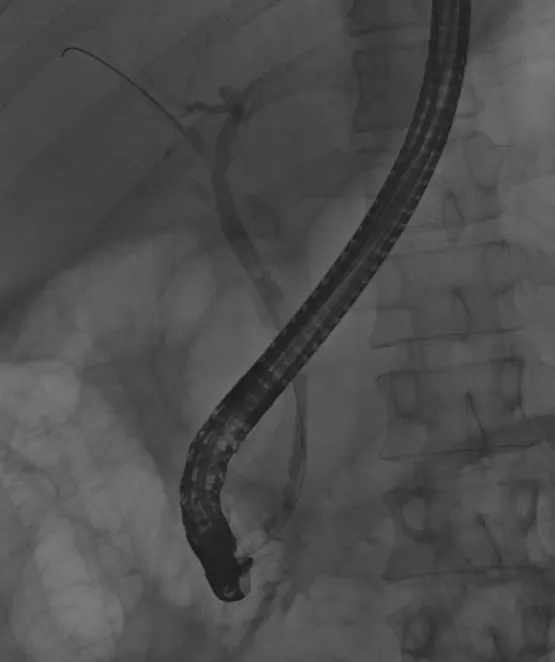

내시경이 고정되지 않았기에 간호사에게 내시경을 단단히 잡아달라고 부탁하였고, 조심스럽게 담관 입구를 찾아 카테터라고 불리는 관을 삽입하였다. 췌관과 담관은 바로 옆에 붙어 있다. 췌관을 건드릴 경우 췌장염을 더 유발할 수 있으므로 시술은 매우 조심스러웠다. 다행히 담관으로 카테터가 들어갔고, 담관을 관찰하였을 때 담관 아래쪽이 췌장염으로 인해 좁아진 것을 확인할 수 있었다.

담관을 조영하여 x-ray 로 확인하는 모습. 위쪽 담관과 비교해서 아래쪽 담관은 막혀 있다.

좁아진 담관에 스텐트라고 불리는 플라스틱관을 삽입하면, 그 관을 통해 담즙이 배출돼서 담도염이 호전되게 된다. 환자의 고통을 달래주면서 조심스럽게 담관 스텐트를 삽입하였다.

담관 내부에 플라스틱 스텐트를 삽입한 모습. 이 스텐트를 통해 담즙이 배출된다.